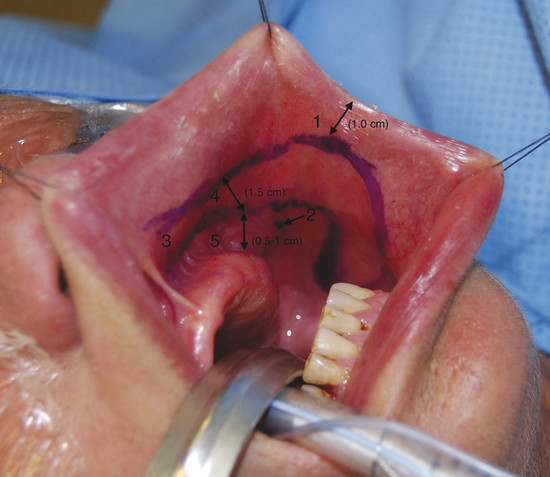

The buccal mucosa is exposed using two traction sutures in the upper and lower lips and a Weider’s tongue retractor (heart-shaped). Alternatively, Senn’s retractors or Gillies skink hooks can be used instead of traction sutures. With the anatomical landmarks in mind, an outline of the flap is drawn on the buccal mucosa (Table 18‑1). The anterior limit of the flap lays 1 cm posterior to the labial commissure to avoid its distortion after closure of the defect. The posterior limit of the flap lies just anterior to Stensen’s duct papillae. A distance of 0.5 to 1 cm is preserved between the posterior margin of the flap and the gingiva to facilitate wound closure (Fig. 18‑3). The use of a Doppler to identify the facial artery has been previously described 3 but will hardly ever modify the flap outline, as it relies on fixed anatomical landmarks. Moreover, the facial artery course outline is not reliable anymore after the mucosal incision because the mucosa becomes loose. Superiorly, the flap base is designed to hinge at the junction between the gingivolabial sulcus and first molar.

The distal end of the flap is designed according to the size and shape of the septal perforation. Measurement of the defect or usage of a template is mandatory and will allow an optimal flap outline. As the width of the FAMM flap is limited by the aforementioned landmarks (usually ~3 cm), the size and axis of the defect will decide whether the flap’s inset will be horizontal or vertical. For a long craniocaudal perforation, the flap’s inset will be horizontal, whereas a tall-vertical perforation will be covered with the flap inserted vertically.